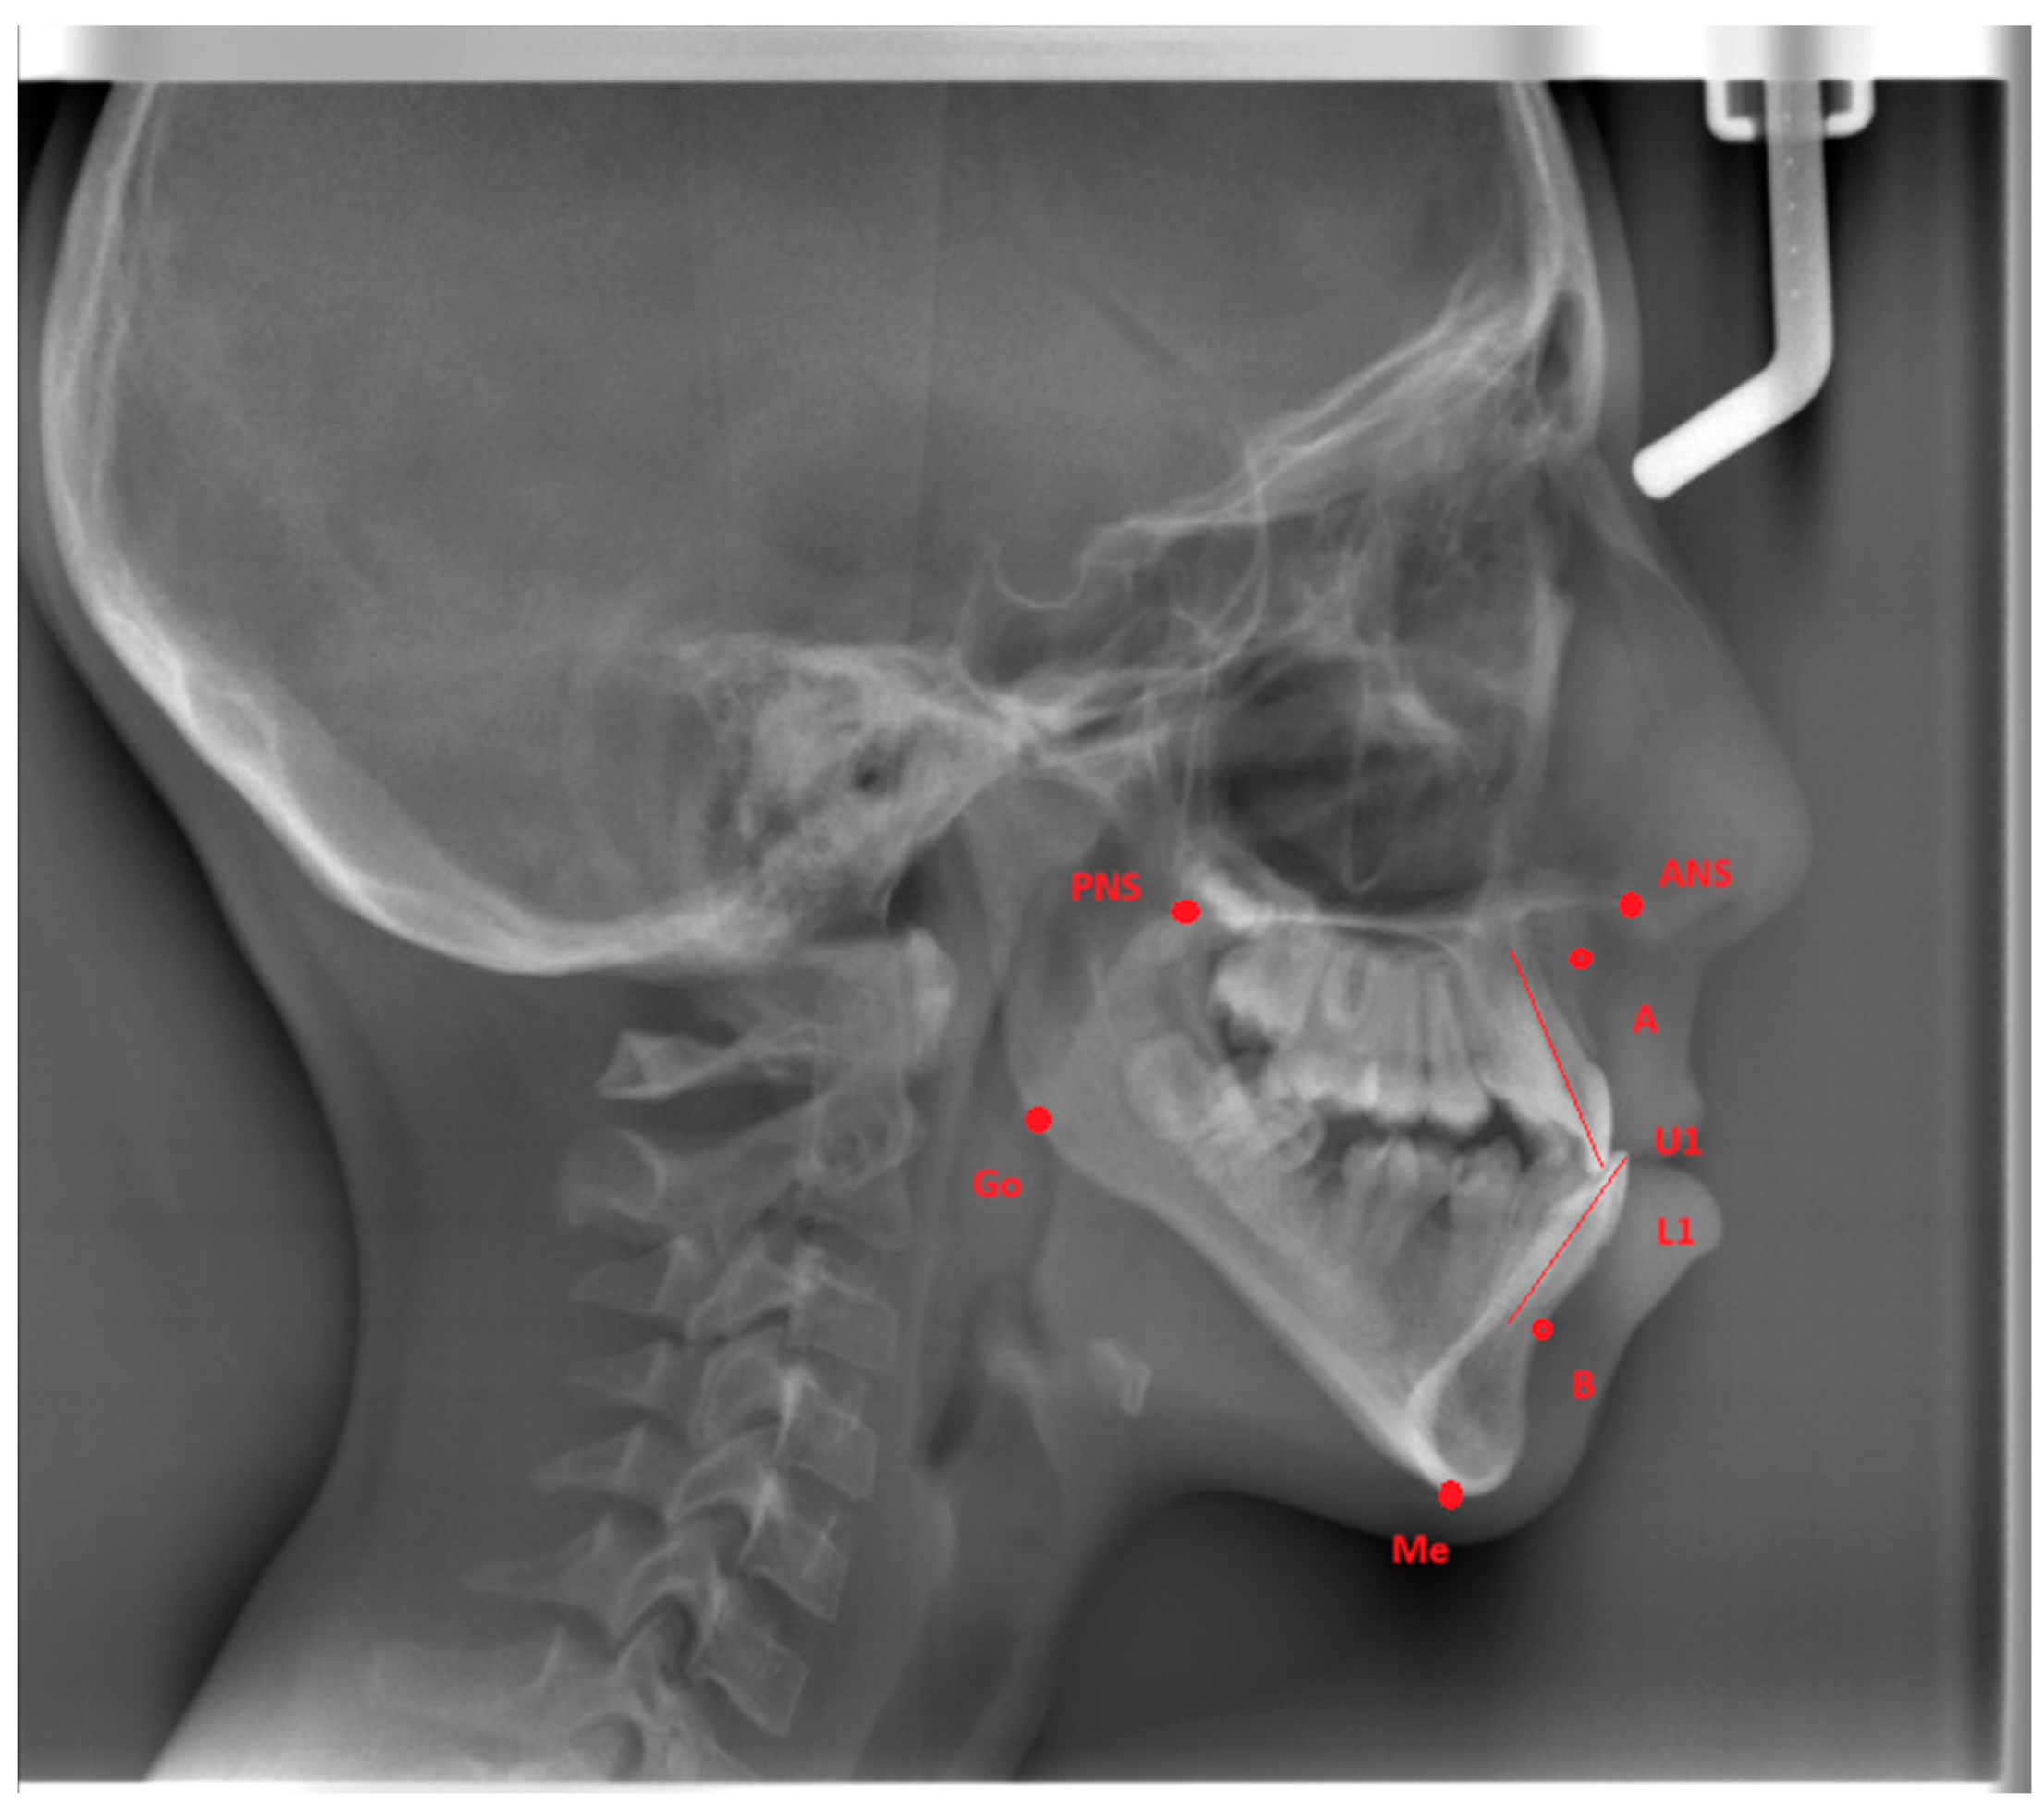

The A point, B point, Anterior Nasal Spine, Posterior Nasal Spine, Gonion, Menton, U1, and L1 were marked (Figure 1) and four measurements were made (Figure 2) on lateral cephalometric radiographs.

Figure 1. Cephalometric reference points. (ANS: The most anterior point of the maxilla at the nasal floor. PNS: The most posterior point of the maxilla at the nasal floor. A point: The deepest point of the anterior maxilla under ANS. B point: The deepest point of the anterior alveolus of the mandible. U1: The line between the incisal tip and the root apex of the upper central incisors. L1: The line between the incisal tip and the root apex of the lower central incisors. Gonion (Go): The meeting point of the posterior border of the ramus and the inferior border of the mandibular corpus. Menton (Me): The most inferior point on the mandibular symphysis.